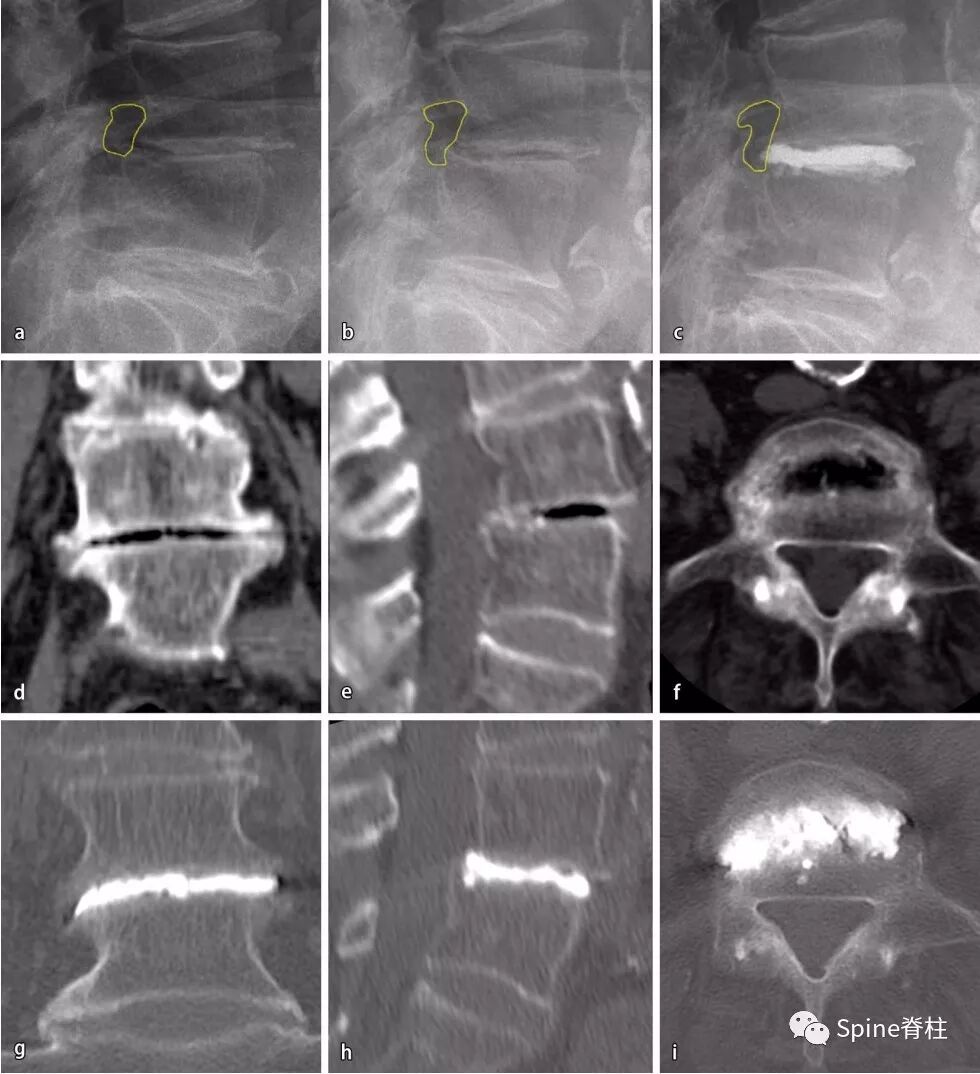

图三:1个节段PCD

a:术前立位侧位X片;

-

b:术前仰卧位侧位X片,注意:神经孔的横截面变大;

c:术后立位侧位x线(横截面保持不变);

d,e:术前CT,病变节段冠状重建,椎间盘间隙有真空现象,同一节段矢状面重建;

f:相同的轴向截面,显示椎间盘内真空征情况;

g,h:术后CT,冠状面重建显示骨水泥位置,同一节段在矢状面重建。

i:横断面情况。